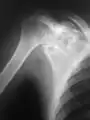

A variety of imaging studies can be used to diagnose chondroblastoma, with radiographs being the most common.[10][8] Laboratory studies are not considered useful.[14] Classical chondroblastoma (appearing on long bones) appears as a well-defined eccentric oval or round lytic lesion that usually involves the adjacent bone cortex without periosteal reaction.[10][13] A sclerotic margin can be seen in some cases.[10][13] For long bone chondroblastomas the tumor is typically contained to the epiphysis or apophysis but may extend through the epiphyseal plate.[10][13] Chondroblastomas are usually located in the medullary portion of bones and can, in some cases, include the metaphysis.[10][13] However, true metaphyseal chondroblastomas are rare and are typically the result of an extension from a neighboring epiphyseal legion.[10][13] Most lesions are less than 4 cm.[10] A mottled appearance on the radiograph is not atypical and indicates areas of calcification which is commonly associated with skeletally immature patients.[10] Additionally, one-third of all cases involve aneurysmal bone cysts which are thought to be the result of stress, trauma or hemorrhage.[10] In cases involving older patients or flat bones, typical radiographic presentation is not as common and may mimic aggressive processes.[10][13]

2. X-ray of chondroblastoma of shoulder blade